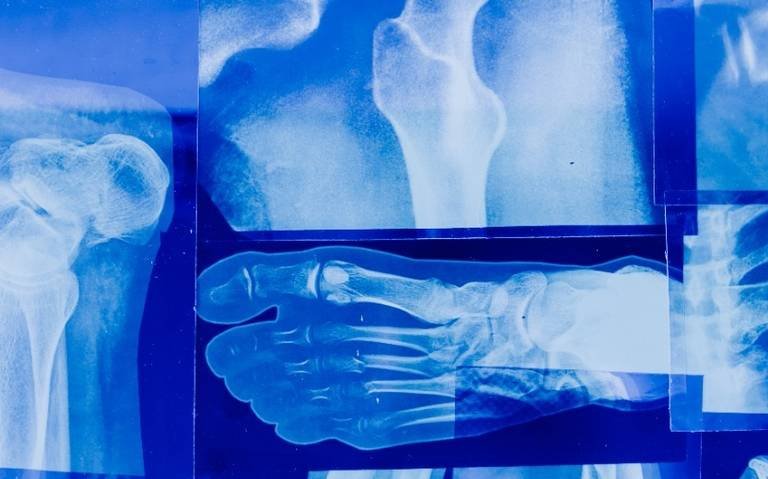

El médico agregó que poer esta razón es importante practicarse una densitometría ósea, estudio que paraermina la densidad y calidad de los huesos, para poder brindar a la persona un tratamiento.

Añadió que la osteoporosis es una enfermedad crónica y progresiva que origina una disminución de la masa ósea, con el aumento de su fragilidad y fracturas.